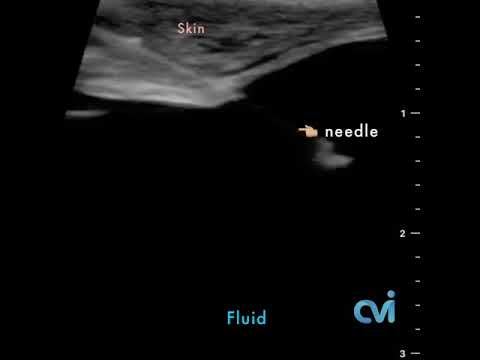

The UFE procedure is performed in a million dollar vascular center using advanced imaging technology with microwires and catheters, which allow the treatment to be performed through a tiny nick in the skin (slightly larger than an IV).

This imaging technology in experienced hands helps guide the microwires and catheters to the fibroids all the way from the leg or arm. As a result the specialist can visualize the anatomy and guide the tools to the area of interest without having to make large incisions or placing a camera into the abdomen as required for other fibroid surgeries.

The patient is given a local and topical anesthetic to numb the skin and a mild sedative, so that the procedure is not painful. A sophisticated X-ray machine that creates moving pictures in “real” time enables the doctor to see the catheter as it is guided through the blood vessels and into the uterine artery.